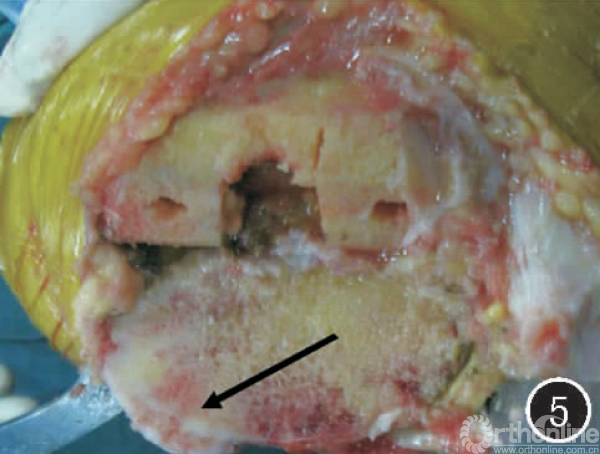

图5屈膝、内翻畸形患者胫骨平台截骨后,见骨赘与正常骨质之间一隐约的白线(箭),为尚未骨化的软骨组织

因此,正确的做法是胫骨平台假体必须要放置在白线之内,否则就要旋转错位。如果我们不将胫骨平台假体放置在白线之内,那就会使胫骨平台假体旋前,进而造成股骨与胫骨的受力点向胫骨平台后方转移,产生胫骨平台后方的应力集中,长期应力集中而造成胫骨平台聚乙烯垫的磨损和破坏。正确的手术操作应该是:把胫骨平台假体放到白线内之后,切除假体没有覆盖的骨赘,这样既矫正了旋转畸形,又能松解膝关节内侧副韧带的紧张(见图6)。